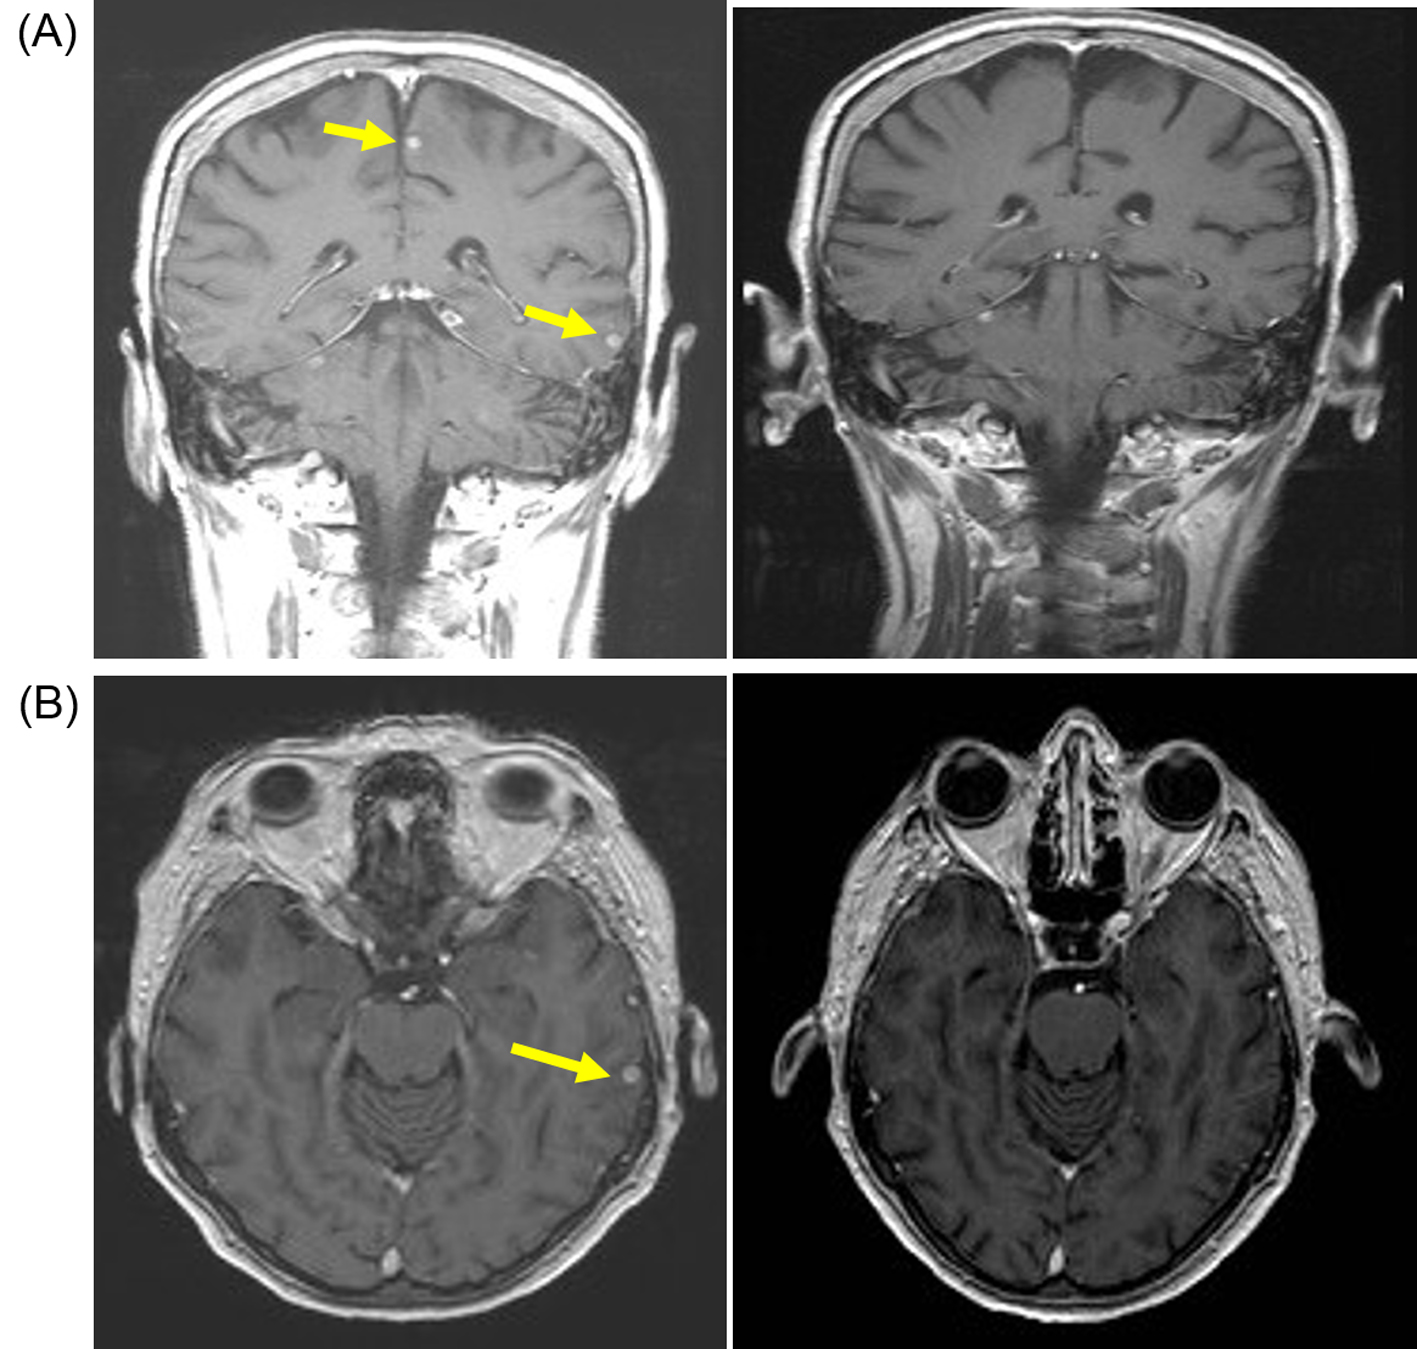

In June 2011 a follow-up CT showed small volume lung metastasis and stable appearances of brain metastasis. There was an improvement in her clinical condition and performance status (WHO grade 1-2), but she had commenced therapeutic anticoagulation with low-molecular weight heparin in view of below-knee deep vein thrombosis and pulmonary embolism. In view of reappearance of lung metastasis, she was commenced on pazopanib 800 mg/day that she tolerated well with no significant toxicities. She underwent repeat imaging 3 months later that showed an improvement in lung metastasis and also response in the brain metastasis (Fig. 2). She continued on pazopanib 800 mg/day, but the dose was reduced to 600 mg/day in December 2011 in view of symptoms of poor appetite and fatigue. Despite the reduction in dose of pazopanib, she continued to have poor tolerance of subsequent cycles and she embarked on treatment “holiday” with discontinuation of pazopanib in March 2012. She had progression-free interval of 11 months, but in February 2013 she developed progressive brain metastasis with enlarging lesion in the left parietal lobe. She recommenced pazopanib at 600 mg/day which she again tolerated poorly and the treatment was discontinued after 4 months in July 2013, but a repeat MRI scan confirmed response with reduction in size of brain metastasis (Fig. 3). She could not re-commence TKI therapy in view of deteriorating general condition, but repeat imaging in January 2014 showed no evidence of disease progression. She died in June 2014 and 40 months after her diagnosis with brain metastasis.

![]() Click for large image | Figure 2. Patient developed response after pazopanib (800 mg/day) with resolution of brain metastasis. (A) Coronal T1-weighted scan with gadolinium contrast demonstrating small sub-centimeter contrast enhancing lesions (yellow arrow) on baseline MRI scan (left panel) that resolved after 3 months of pazopanib (right panel). (B) Axial T1-weighted baseline MRI scan with gadolinium showing small sub-centimeter metastasis (left panel) that resolved after 3 months of pazopanib (right panel). |